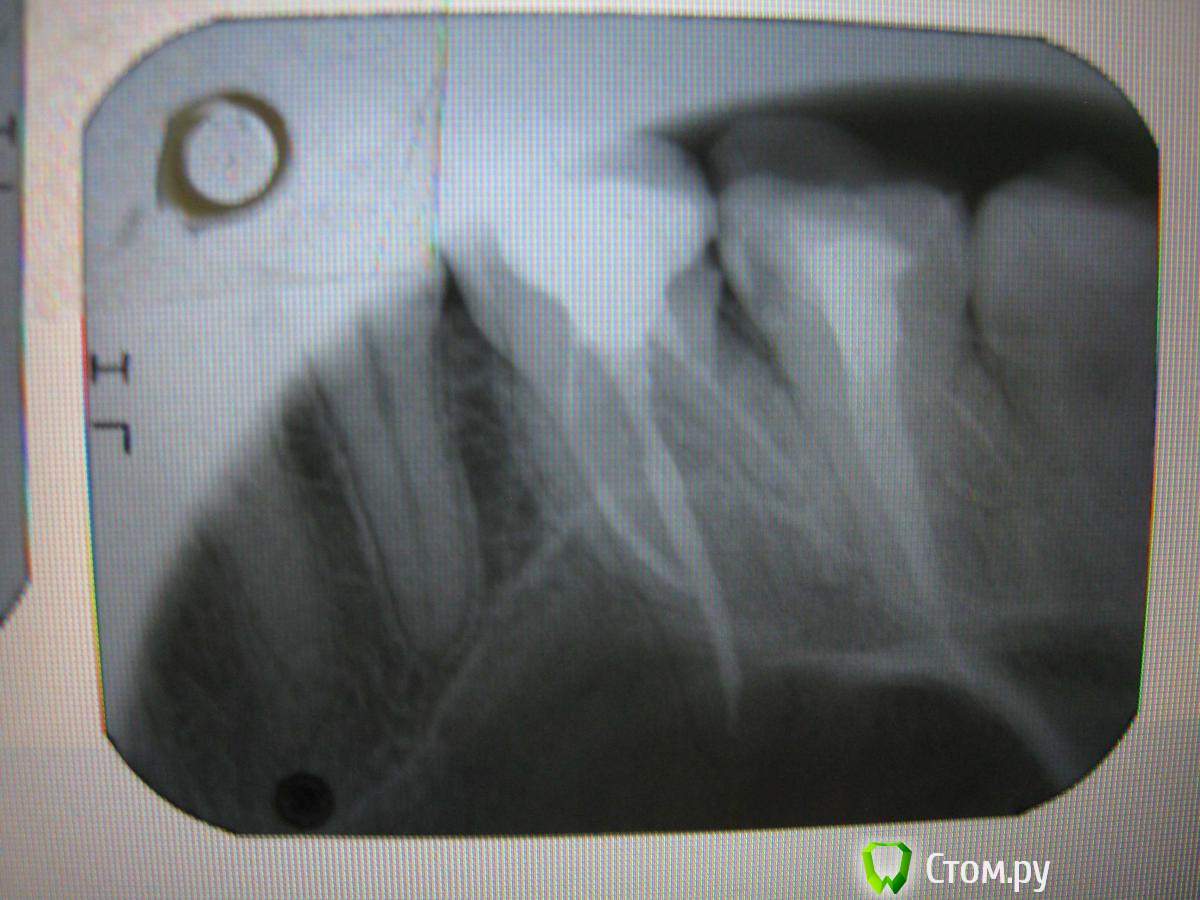

KateDav Опубликовано 22 мая, 2014 Автор Поделиться Опубликовано 22 мая, 2014 (изменено) Снимки. На семерке третий канал который плохо видно, плохо запломбирован?? Жду ваших комментариев. Изменено 22 мая, 2014 пользователем KateDav Ссылка на комментарий

red_butler Опубликовано 22 мая, 2014 Поделиться Опубликовано 22 мая, 2014 повторное лечение корневых каналов 6 и 7 зубов, ищите эндодонтиста с микроскопом 1 Ссылка на комментарий

Гарриевич Опубликовано 22 мая, 2014 Поделиться Опубликовано 22 мая, 2014 Не однородное, не плотное заполнение корневых каналов. Отсутствие должного расширения каналов, что может навести на мысль о пломбировке па той или одним штифтом 1 Ссылка на комментарий

red_butler Опубликовано 22 мая, 2014 Поделиться Опубликовано 22 мая, 2014 + к вышесказанному, в 7 зубе отломок инструмента Ссылка на комментарий